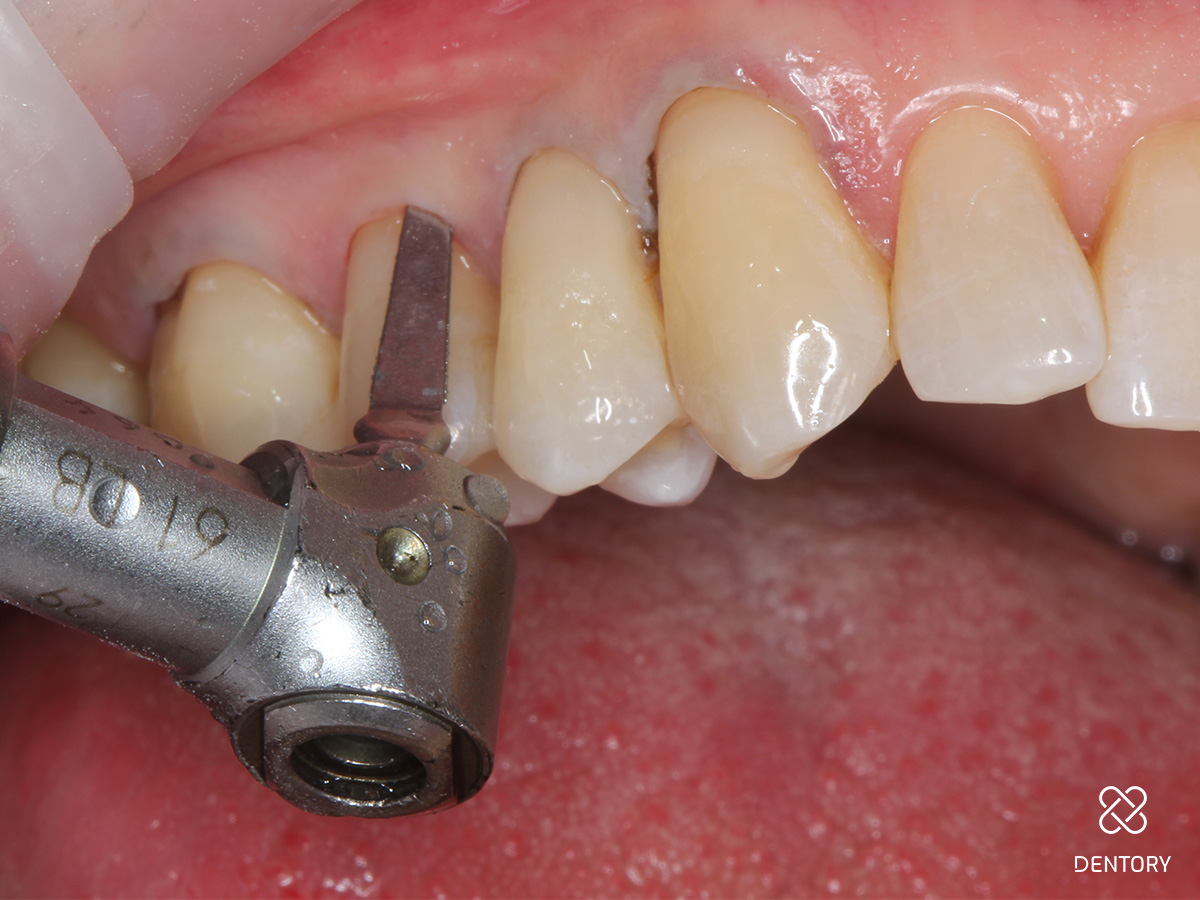

Abbildung 2

Beurteilung der Lage der Kavität nach zervikal. Liegt der Defekt supragingival, kann auf den Sulkus-Faden verzichtet werden. Liegt der Defekt äquigingival oder subgingival wird ein 00-Faden gelegt.